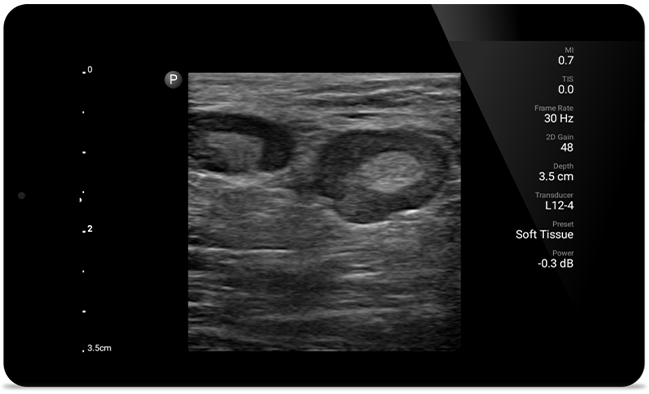

Get the clarity of larger ultrasound systems with Lumify

SonoCT reinforces real tissue imaging while eliminating random artifacts. This technology produces images superior to conventional imaging in up to 94% of patients.